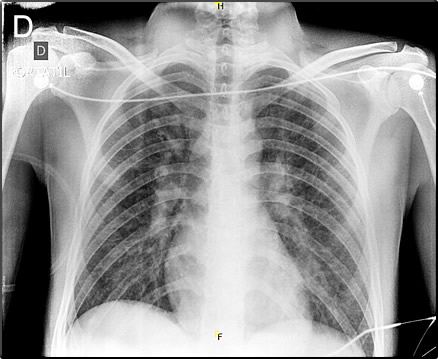

|

![]() Discussion: ELISA IgM for Yellow fever on day 6 of illness was positive at NIH-Peru. PCR and culture were not performed. HBsAg and Anti HBc negative, HBsAg-Ab positive (vaccinated), Anti HCV negative, IgM for hepatitis A negative, ELISA IgM and IgG for Dengue negative. IFI IgG Ab and total Ab for Rickettsia negative. IgM leptospira negative, at the NIH-Peru. IgM for yellow fever typically is positive by day 7 of illness compared to day 5 for a dengue IgM. Fulminant yellow fever is the true prototypical viral hemorrhagic fever (unlike Ebola Virus Disease in the recent African outbreak) where patients bleed out and the liver dissolves [see recent review of yellow fever in J Clin Virol. 2014 Oct 24. pii:S1386-6532(14)00369-2]. Pathophysiological features are shared with several unrelated diseases except that the severity and extent of the hepatonecrosis is greatest in yellow fever patients. The hallmarks of the full yellow fever syndrome include the pathognomonic triad of hemorrhagic fever with jaundice and renal disease. Other viral hemorrhagic fevers may present with either jaundice or with renal disease, but the combination should always suggest yellow fever if there has been appropriate exposure according to the epidemiologic history. • Dengue hemorrhagic fever is co-endemic in many areas but the pathophysiology is related to increased capillary leakage and illness is usually accompanied by a history of rash at some point in the illness. Hepatitis occurs only occasionally and is mild. Renal involvement does not occur with dengue and the finding of significant proteinuria (such as in this case) on a urine dipstick should always suggest yellow fever over dengue even early in the course of the clinical evolution. Mild cases of yellow fever cannot be distinguished clinically from falciparum malaria, leptospirosis, viral hepatitis, typhoid, rickettsial disease, hepatotoxin ingestion, or relapsing fever. More than 80% of yellow fever infections are symptomatic and the incubation period is usually very short, 3 to 6 days. After an acute febrile illness with headache and myalgia without rash, which likely represents the peak viremia, there may be a period of remission. Severe cases most often do not follow that course and progress quickly to multi-organ failure with liver failure as the main determinant of mortality. Severe oliguric renal failure very early in the course as in this case is unusual. With biphasic illness, fever may then resume with back pain, nausea, vomiting, and mental status changes. Black vomitus (hematemesis) is commonly described. In fatal cases death usually occurs 6 to 10 days into the illness. Pathologically, yellow fever causes hepatocellular and Kupffer cell infection. There is mid-zonal hepatocellular necrosis with a minimal inflammatory response. So-called Councilman bodies and microvesicular fatty change is seen. A marked decrease of hepatic transaminases and bilirubin just before death likely represents near total destruction of functioning hepatocytes. In our patient, transaminases decreased from a peak of 300 times normal to 10 times normal (see below). In 2014, 17 yellow fever cases were confirmed in Perú, with 7 in San Martin and 2 in Junin (Chanchamayo). In 2013 there were 21 cases with a case-fatality rate of 64%. The total number of reported cases in Chanchamayo is decreasing in recent years. In many recent years Perú has reported more cases of yellow fever than other countries in South America combined; this may reflect the excellent surveillance system. As with other flaviviruses there is no specific treatment for yellow fever, making prevention by use of 17D yellow fever vaccine (essentially 100% effective) imperative. Most individuals in endemic areas (Amazon basin and sub-Saharan Africa) have variable access to vaccines but the much higher general vaccine coverage in endemic areas of Latin America account for the relatively few annual cases compared to 50,000/yr in Africa. Nonetheless, there is dramatic under-use of vaccine by travelers and expatriates. At least 10 unvaccinated short-term travelers to endemic areas have died of yellow fever since 1995. Data indicates that the number of unvaccinated travelers visiting risk areas is substantial. In Perú specifically, government vaccination programs cover the endemic areas, but residents of non-endemic areas who travel to the jungle are often poorly informed of the risk. Soon after presentation, the patient developed respiratory distress with the following lab parameters: Arterial blood gases: pH 7.30, pCO2 18.4, pO2 49.2, SO2 77.9 (FiO2 of 21%, PO2/FiO2: 234), HCO3 9.0, serum lactate 5.0. Pulmonary involvement early on the course of illness is also seen, the majority of patients then develop ARDS. Chest X-ray from the ER is shown (Image D). After intubation and mechanical ventilation, interventions included acetylcysteine, fresh frozen plasma, dialysis, RBC and cryoprecipitate transfusions were instituted for the typical coagulopathy in this disease. Bleeding through the dialysis catheter insertion site (up to 800cc) and coffee grounds through the orogastric tube (up to 200cc) ensued. Nosocomial pneumonia with Acinetobacter ensued despite empiric antibiotic therapy from the outset and he remains stable but intubated and remains on dialysis. Liver function has stabilized but may reflect massive hepatic destruction. Total bilirrubin 6.2 mg/dL (conjugated 3.4 mg/dL, unconjugated 2.8 mg/dL). AST 189 U/L, ALT 361 U/L, AP 119 U/L, GGT 265 U/L, LDH 1177. Both other yellow fever cases seen during earlier Gorgas Courses (2015-2; 2002-10) have been fatal. Of note, his girlfriend was admitted one day later with a milder febrile illness, serology for yellow fever was also positive. She is recovering uneventfully. Sexual transmission has not been reported in yellow fever. By report the 2 patients did not have sexual relations during or after the trip. |